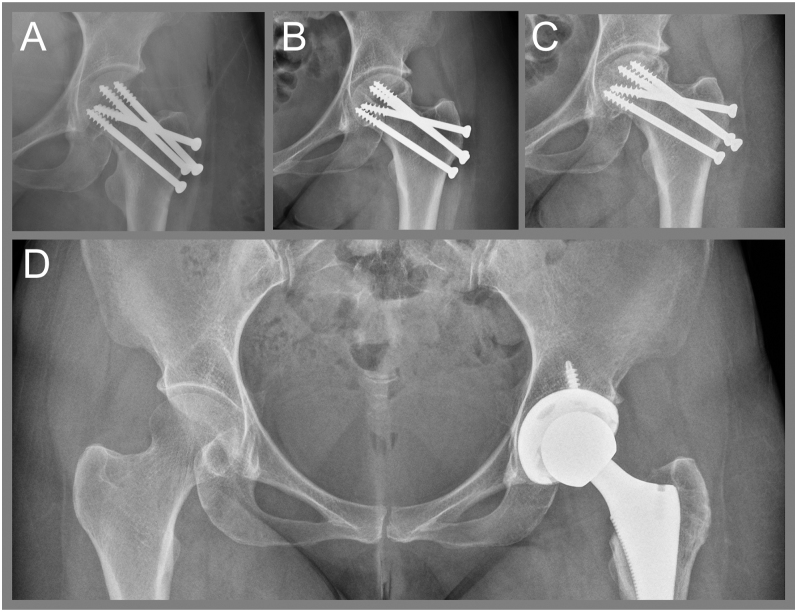

摘要:醋酸甲羟孕酮(DMPA)是一种高效的注射避孕药,但在一些研究中,由于它抑制下丘脑-垂体-卵巢轴,因此与骨密度(BMD)降低和骨折风险增加有关。在此,我们提出诊断具有挑战性的情况下,绝经前妇女不寻常的髋部骨折和长期使用肌内注射DMPA。全外显子组测序揭示了一种罕见的ALPL基因杂合变异,该变异可能导致成人发病的低磷酸盐症(HPP)。然而,它被归类为一个未知意义的变体。我们的病例强调了长期使用DMPA的骨折风险,DMPA在低收入和中等收入国家广泛用作仅使用孕激素的避孕方法。临床医生应告知妇女长期使用DMPA避孕对骨骼健康的潜在不利影响,并建议她们养成健康的生活习惯,摄入足够的钙和维生素D。学习要点:有证据表明肌内注射醋酸甲羟孕酮(DMPA)通过抑制下丘脑-垂体-卵巢轴对骨密度产生负面影响。然而,由于缺乏骨折发生率的数据,DMPA导致骨脆性骨折的风险仍然不确定。在这里,我们提出了一个绝经前妇女不寻常的髋部骨折和长期使用肌内DMPA避孕的历史。我们的病例也强调了患者的临床表现是解释基因测序结果的关键。

Summary: Depot medroxyprogesterone acetate (DMPA) is a highly effective injectable contraceptive, but is associated with reduced bone mineral density (BMD) and increased fracture risk in some studies because it inhibits the hypothalamic-pituitary-ovarian axis. Herein, we present the diagnostic challenging case of a premenopausal woman with an unusual hip fracture and prolonged use of intramuscular DMPA injection. Whole-exome sequencing revealed a rare heterozygous variant of the ALPL gene, which could cause adult-onset hypophosphatasia (HPP). However, it was classified as a variant of unknown significance. Our case highlights the fracture risk from long-term use of DMPA, which is widely used as progestogen-only contraceptive method in low- and middle-income countries. Clinicians should inform women on the potential adverse effect of prolonged use of DMPA for contraception on bone health and advise them to adopt healthy lifestyle habits, with adequate calcium and vitamin D intake.

Learning points: Evidence shows that intramuscular depot medroxyprogesterone acetate (DMPA) negatively affects BMD by inhibiting the hypothalamic-pituitary-ovarian axis. However, the risk of bone fragility fracture from DMPA remains uncertain because of paucity of data on fracture incidence. Herein, we present a case of a premenopausal woman with an unusual hip fracture and a history of prolonged use of intramuscular DMPA contraception. Our case also highlights that the patient's clinical presentation is essential for interpreting genetic sequencing results.